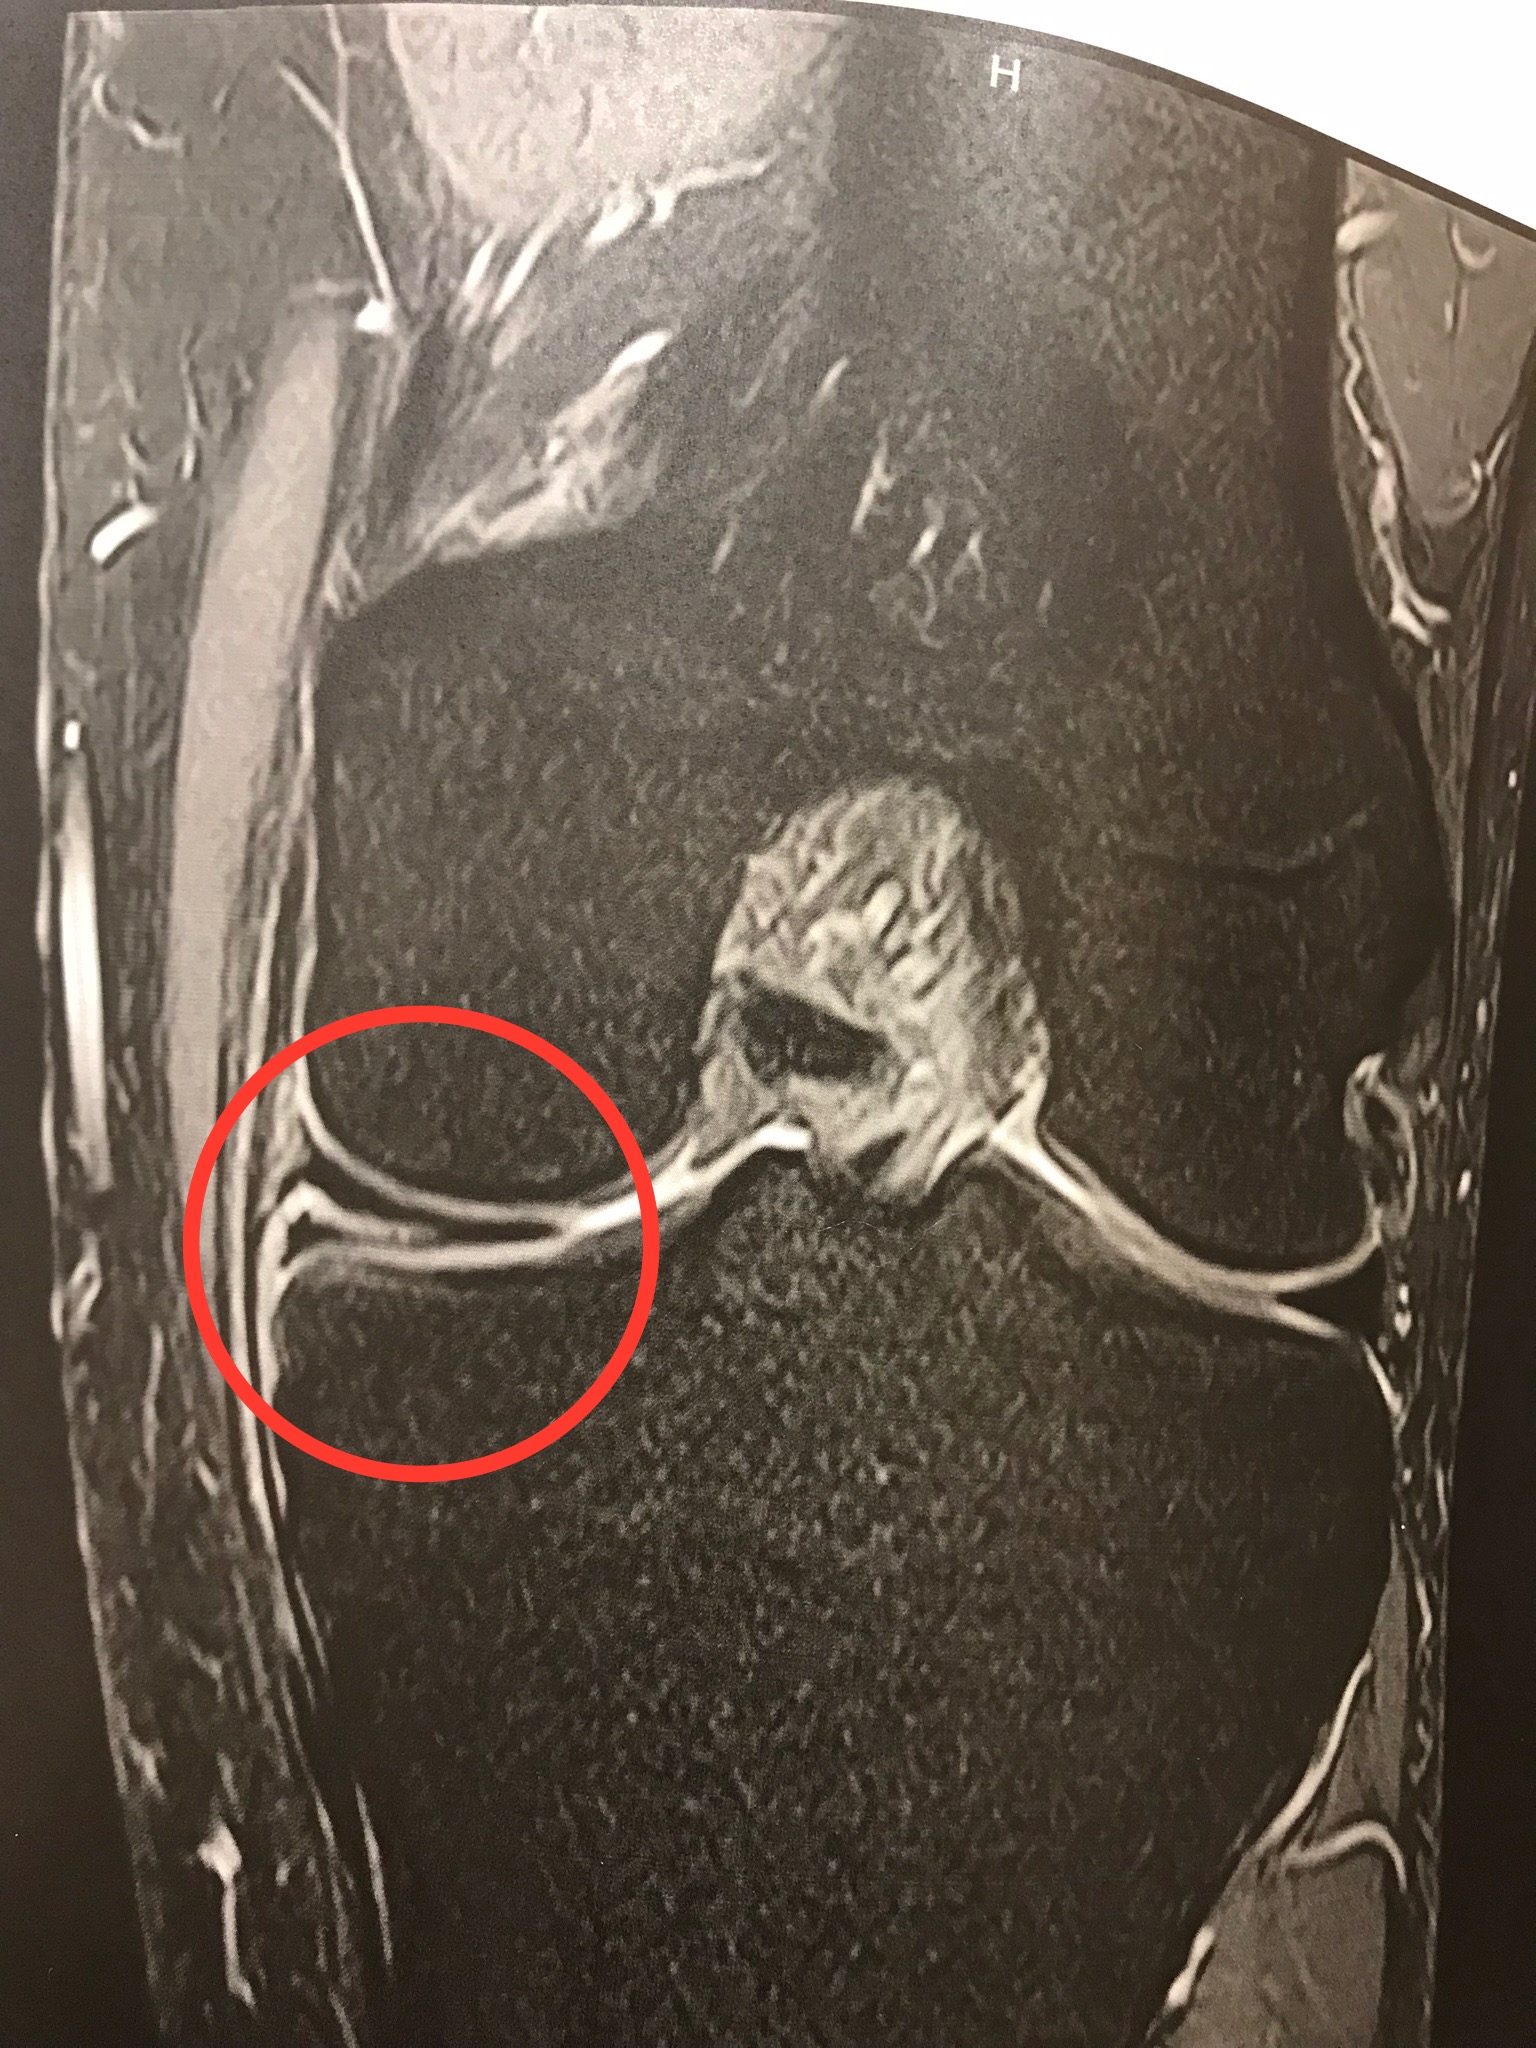

度々書いていることですが、自分は約2年前に半月板断裂の怪我を負いました。

半月板とは大腿骨と脛骨の間にあるクッションで、外周のごく一部を除いて血行がなく、治癒することのない部位となります。

なので自分の場合は内転筋を鍛えたり、毎日ストレッチをして、なんとかごまかして凌いでいる状況なのですが、以前より断裂幅が進行しているような、そんな気がしています。

痛む頻度が多くなっているのです。